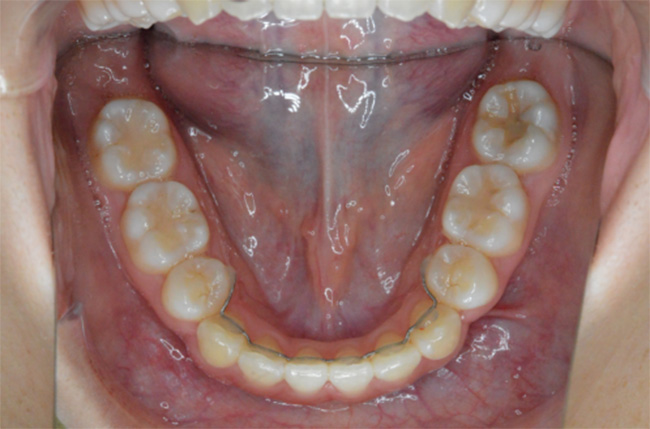

| 治療方法 | 上下顎小臼歯4本抜歯、ワイヤー矯正 |

| 治療内容 | 抜歯のスペースを使用して、上下前歯を後退させた |

| 治療期間 | 2年1ヵ月 |

| 治療費 | 979,000円(矯正装置・調整料・リテーナー・歯科矯正用アンカースクリュー・矯正治療後2年間経過観察料を含む) ※2025年10月以前の料金となります。 |